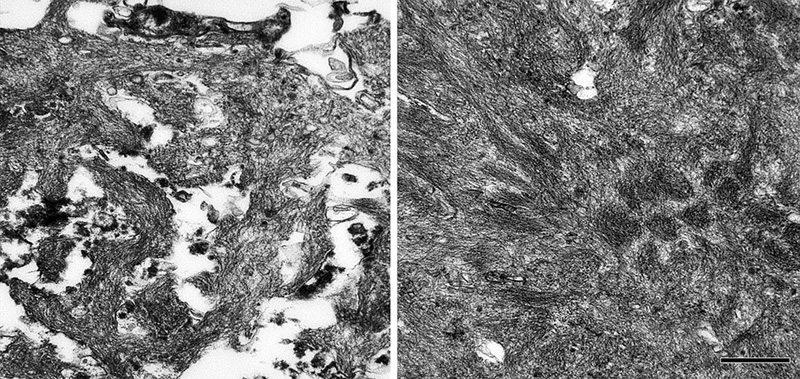

The core-space-corona arrangement of Aβ is a notable structural feature of classical Aβ plaques that was noted in several early investigations (reviewed in [116, 119, 120]). These subdivisions of plaques have been given various designations in the early literature, for instance Zentrum or Kern, Hof, Ring, etc.10 In tissue that has been immunostained for Aβ, classical Aβ plaques have a condensed core of Aβ-amyloid surrounded by an optically clear region with little Aβ, and then an outer corona of more diffuse Aβ [195] (see Figure 1); the relatively clear intermediate space and the outer corona are occupied by neuronal and glial elements (which are considered in more detail in Section 6).

Viewed in the electron microscope, Aβ-amyloid fibrils in the plaque core are densely packed and often bundled to form a patchy matrix, and viable cellular processes there are largely absent. The more loosely organized Aβ-amyloid sheaves in the space and corona interdigitate with cellular elements such as glial processes and neurites (Figure 12; see also Figures 18 and 20). Embedded in the fibrillar meshwork of amyloid in plaques, various small, spherical particles can be seen (Figure 13). The origin and significance of this material is obscure, but it could account for some of the non-Aβ substances that have been detected in the cores of Aβ plaques (see Section 7). One possibility is that these vesicles originate from intracellular multivesicular bodies, which have been shown experimentally to be an important site of APP/Aβ biology [196-201]. In this regard, vesicular structures ranging from 50 to 300nm in diameter have been reported among the amyloid fibrils in a cell culture model of Aβ amyloid deposition [202].

Figure 12. Ultrastructure of fibrillar Aβ in the plaque corona (left) and core (right) in an AD patient. Bar = 500nm for both images.